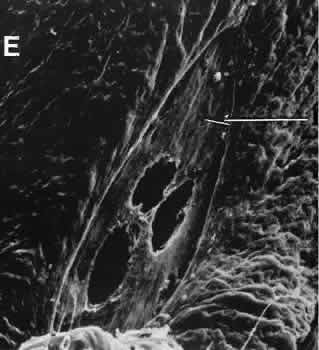

Cyclocryotherapy, cyclodiathermy (Fig. 20), and therapeutic ultrasonography apply energy directly to the pars plicata and cause lysis of the ciliary muscle and occlusion of the vascular supply, leading to extensive necrosis and scarring. Pressure lowering is accomplished by a reduction of aqueous production. Heat applied to the sclera may cause necrosis and localized scleral thinning. Cold applied to the sclera, unless extreme, does not cause any clinical or histologic changes.

Fig. 20. Cyclodiathermy treatment of the ciliary body to control glaucoma. A. Gross photograph illustrates extensive areas of depigmentation mainly in the region of the pars plana (arrows) rather than the pars plicata. B. Light micrograph of the region of the pars plana illustrates an extensive area of tissue degeneration of the pars plana (between arrows) in the late postoperative course. C. Light micrograph of the destructive effects of cyclocryotherapy also in the region of the pars plana and pars plicata. The ciliary epithelium in the early postoperative period is necrotic and cystic. (Hematoxin-eosin stain; A, × 8; B, × 16.)